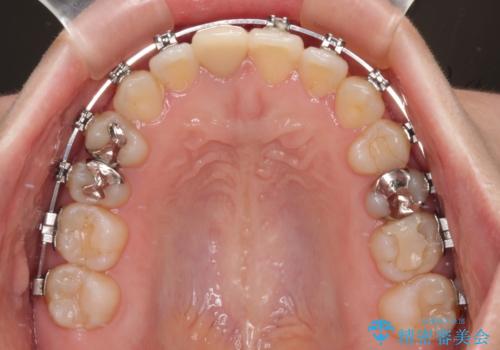

上顎歯列は歯の移動量が少なかったため、セラミッククラウンは装置を装着せずに治療を終えることができました。

- メタルブラケット

- 1年5ヶ月